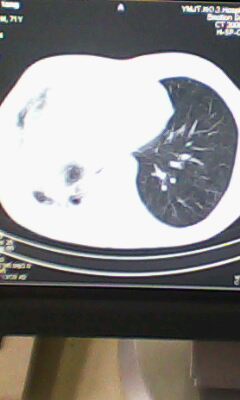

标题: CT25675:男 71 肺癌部分切除术后 3年 [打印本页]

标题: CT25675:男 71 肺癌部分切除术后 3年

两肺感染性病变,右侧肺膨胀不全,左侧上叶结节影及左侧颈部淋巴结肿大建议复查。

右肺癌切除术后。

右肺炎症,左肺炎症。

1.右肺符合肿瘤切除术后ct表现。

2.左肺炎症。

术后改变,双肺内纤维索条影考虑与放疗有关。